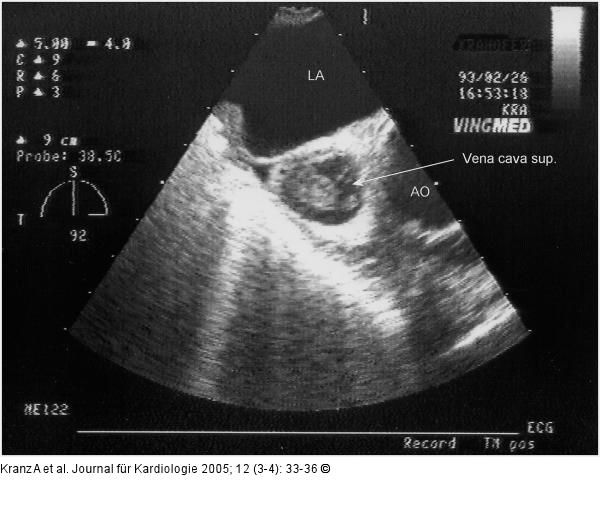

Abbildung 3a-b: Vena cava sup. - Subtotale Thrombose |

Abbildung 3b

Abbildung 3a-b: Vena cava sup. - Subtotale Thrombose